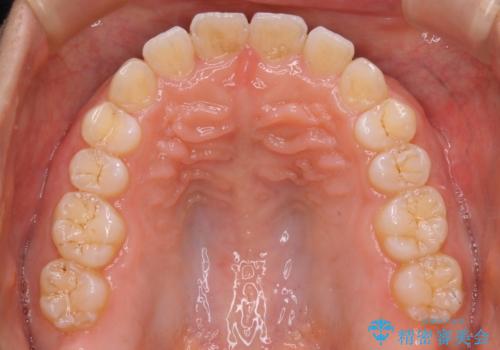

マウスピースで効率的にすきっ歯を治す

- 矯正治療を主訴にご来院されました。

すきっ歯と噛み合わせの治療をしたいとのことで、インビザラインを用いて矯正治療を行うこととなりました。

すきっ歯の場合、ガタつきを治したりするのに必要なスペースが最初から空いているため、そのスペースを利用して比較的短期間で効率よく治療を進めることが可能となります。